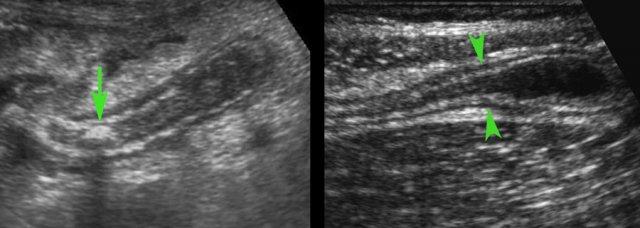

Mô mỡ viêm

Mô mỡ đầu tiên bị ảnh hưởng trong viêm ruột thừa là mạc treo ruột thừa (meso-appendix).

Mạc treo ruột thừa bình thường có thể được nhận diện khi được bao quanh bởi một ít dịch trong phúc mạc như ở bệnh nhân này, và có đặc điểm tăng âm vừa phải, mềm mại và dễ ép xẹp.

Khoảng 4-6 giờ sau khi khởi phát triệu chứng, tình trạng viêm bắt đầu ảnh hưởng đến mạc treo ruột thừa, khiến nó to hơn, tăng âm hơn và không thể ép xẹp (đầu mũi tên).

Sự sản xuất fibrin tiếp theo trên bề mặt thanh mạc gây ra viêm phúc mạc khu trú, dẫn đến hiện tượng chuyển đau điển hình từ vùng quanh rốn hoặc thượng vị sang hố chậu phải.

Điều thú vị là trong giai đoạn sớm của viêm mô mỡ, siêu âm nhạy hơn CT.

Ở bệnh nhân này với đau hố chậu phải kéo dài 18 giờ, CT chỉ cho thấy hình ảnh thâm nhiễm mỡ tối thiểu xung quanh ruột thừa 8,5 mm (mũi tên).

Siêu âm với kỹ thuật ép có kiểm soát đã cho thấy rõ ràng mô mỡ viêm tăng âm, không thể ép xẹp (đầu mũi tên) xung quanh ruột thừa.

Ở giai đoạn muộn hơn của quá trình bệnh, mô mỡ xung quanh ruột thừa có xu hướng tăng thể tích.

Đây là mạc nối mỡ đã di chuyển về phía ruột thừa trong nỗ lực bao bọc tình trạng thủng sắp xảy ra.

Ép ngắt quãng từ từ là cách tốt nhất để xác định mô mỡ viêm không thể ép xẹp.

Việc ép các quai ruột nằm ở phía trước cũng giúp giảm ảnh hưởng tiêu cực của hơi trong lòng ruột.